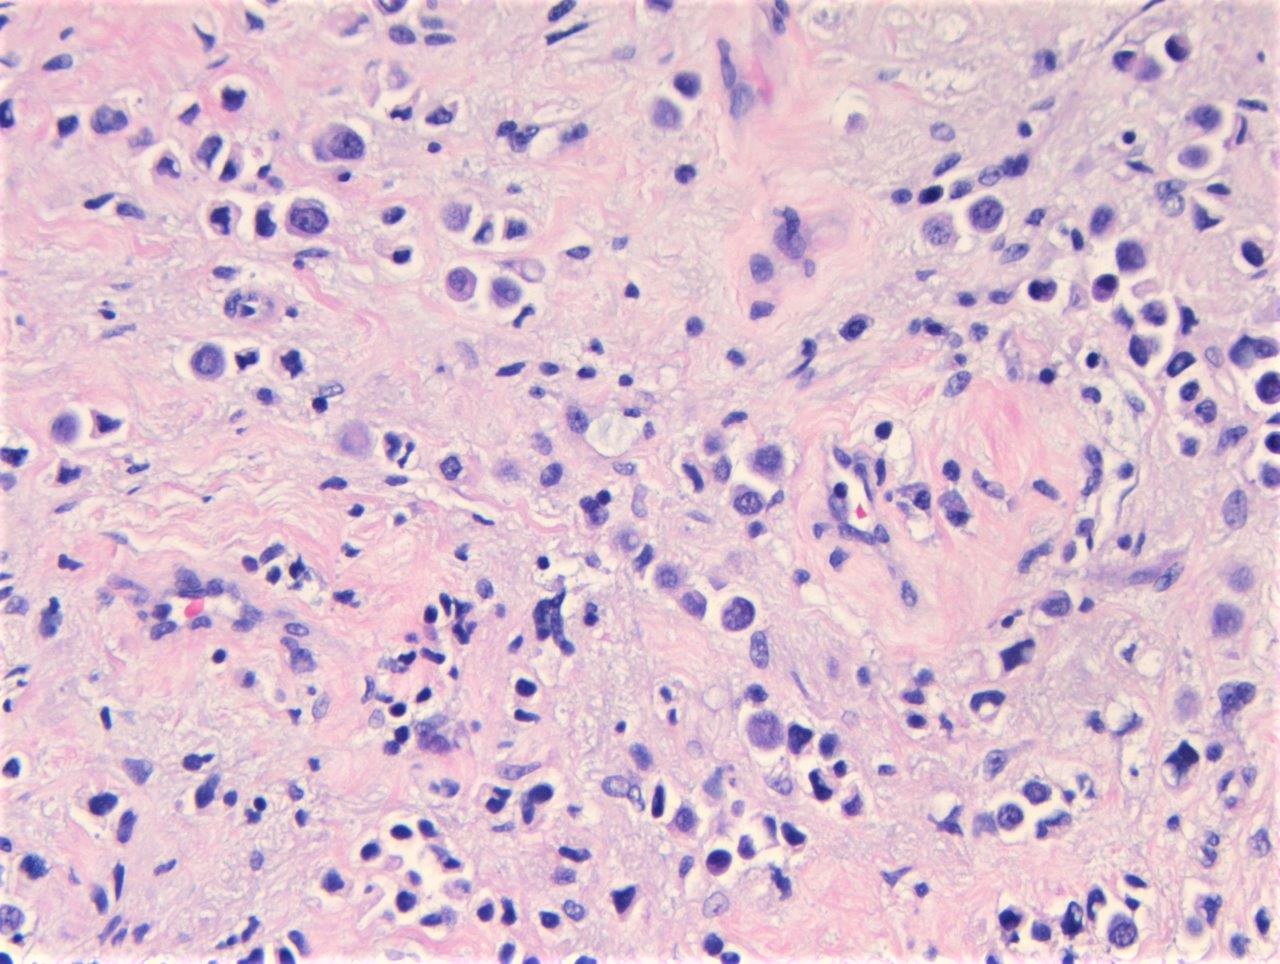

Microscopic (histologic) description

- Discohesive single cells with eccentrically placed nuclei and abundant eosinophilic cytoplasm

- Often deeply infiltrative but with minimal stromal reaction (Eur Urol Focus 2020;6:653)

- Classic: signet ring-like morphology, singly scattered and discohesive in loose aggregates forming cords (Hum Pathol 2019;90:27)

- Pleomorphic: similar to classic but with pleomorphic nuclei and more atypia; can be rhabdoid and bizarre appearing (Hum Pathol 2019;90:27)

- Despite resemblance to signet ring carcinoma cells, notably lack extracellular mucin, contrasting to signet ring adenocarcinoma (Acta Cytol 1991;35:277, Am J Surg Pathol 1991;15:569)

Microscopic (histologic) images

Contributed by Timothy Isaac Miller, M.D., M.A., Nicole K. Andeen, M.D. and Maria Tretiakova, M.D., Ph.D.

Contributed by Lisa Han, M.D. and Ricardo Lastra, M.D. (Case #510)